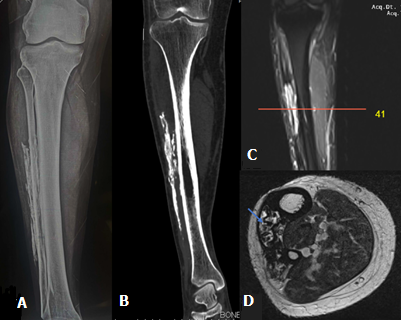

A 50-year-old male presented with a long-standing, slowly progressive, hard swelling over the anterolateral aspect of the right leg. He reported a history of snake bite to the same limb 20 years earlier, which was associated with severe local tissue injury. There was no history of recent trauma, constitutional symptoms, or clinical signs of active infection. Plain radiograph of the right leg demonstrated sheet-like intramuscular calcification along the lateral aspect of the tibia without cortical erosion or periosteal reaction. Non-contrast computed tomography (CT) revealed well-defined linear intramuscular calcifications with central areas of low attenuation suggestive of necrosis within the anterior compartment of the right leg. Magnetic Resonance Imaging (MRI) of right leg demonstrated linear sheet-like intramuscular areas of T1- and T2-hypointensity corresponding to calcifications, with heterogeneous central signal intensity involving the tibialis anterior muscle. The differential diagnosis of such radiological features in the lower limb include; myositis ossificans, soft tissue sarcomas, and chronic expanding hematoma. Myositis ossificans classically demonstrates a zonal pattern of peripheral mature ossification with central lucency on radiographs or CT, which is not identified in this lesion, as there is no organized cortical bone formation. Soft tissue sarcoma may present with irregular or amorphous calcifications, a solid enhancing soft-tissue component, and occasionally cortical erosion or periosteal reaction-features that are not observed in our case. Chronic expanding hematoma can show a well-defined capsule, internal fluid-fluid levels, and a hemosiderin rim on MRI. However, the plaque-like peripheral dystrophic calcification along a single muscle compartment is more typical of calcific myonecrosis. The absence of aggressive characteristics and the presence of fusiform compartmental involvement with sheet-like calcification support the diagnosis. Taken together, the imaging findings are most consistent with calcific myonecrosis rather than the above differentials.